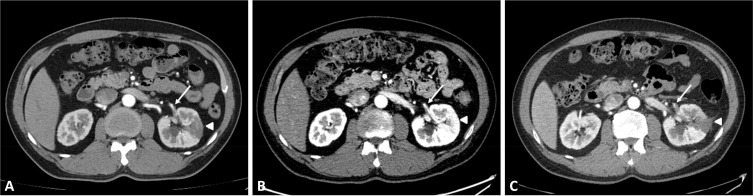

虽然肾梗塞(RI)并不是一种罕见疾病,但其结果却没有得到很好的记录。此外,RI 的一过性缓解和复发也没有通过影像学检查记录下来。我们报告了一例特发性 RI 病例,通过连续计算机断层扫描(CT)显示,该病在一过性缓解后的短时间内又复发了。一名 53 岁的男子被诊断为 RI,转入急诊室。在当地医院进行的腹部 CT 扫描显示左肾有节段性楔形灌注缺损,左肾动脉前段分支有局灶性血栓性充盈缺损。由于他的左侧腹痛有所改善,在首次 CT 扫描 6 小时后再次进行了 CT 扫描。复查 CT 显示,肾动脉内的血栓仍然存在,但灌注缺损已自行消退。我们开始使用非分数肝素进行抗凝治疗。住院第六天,左侧腹痛再次出现,促使我们再次进行了 CT 扫描。后续的 CT 扫描证实,RI 在之前的同一部位复发。我们继续进行抗凝治疗,并改用华法林。治疗后,他的症状有所改善,并已出院。正如我们的病例所示,RI 可在任何时候复发,即使在自发缓解后也是如此。因此,密切监测 RI 缓解的患者是否再次出现症状至关重要,即使在短时间内也应重复进行放射学评估。

Although renal infarction (RI) is not a rare disease, its outcomes have not been well-documented. Furthermore, transient resolution and recurrence of RI have not been captured through imaging. We report a case of idiopathic RI that recurred within a short period following transient resolution, as demonstrated by serial computed tomography (CT). A 53-year-old man diagnosed with RI was transferred to the emergency room. An abdominal CT scan at the local hospital revealed a segmental wedge-shaped perfusion defect in the left kidney and a focal thrombotic filling defect in the anterior segmental branch of the left renal artery. Since his left flank pain improved, another CT scan was performed again 6 hours after the initial CT scan. A repeat CT scan showed that the thrombus in the renal artery remained, but the perfusion defect had spontaneously resolved. We initiated anticoagulant therapy using unfractionated heparin. On the sixth day of hospitalization, the left flank pain recurred, prompting another CT scan. The follow-up CT scan confirmed that RI had recurred in the same area as before. We continued anticoagulant therapy and switched to warfarin. After treatment, his symptoms improved, and he was discharged. RI can recur at any time, even after it has spontaneously resolved, as evidenced by our case. Therefore, it is crucial to closely monitor patients who experience resolution of RI for any recurrence of symptoms, and repeat radiological evaluation should be performed even within a short period.